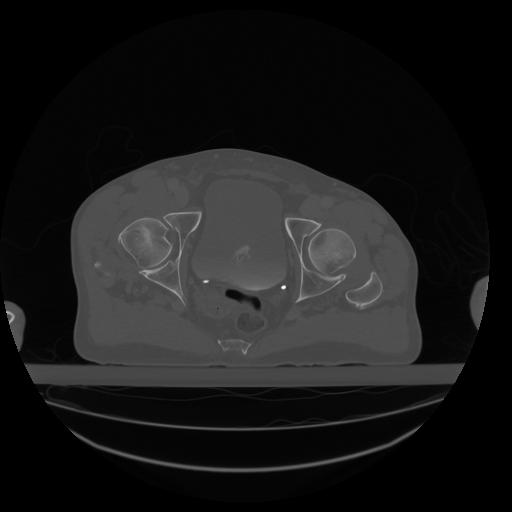

34 CUERPO,CE,Vol,1.0,CUERPO,,